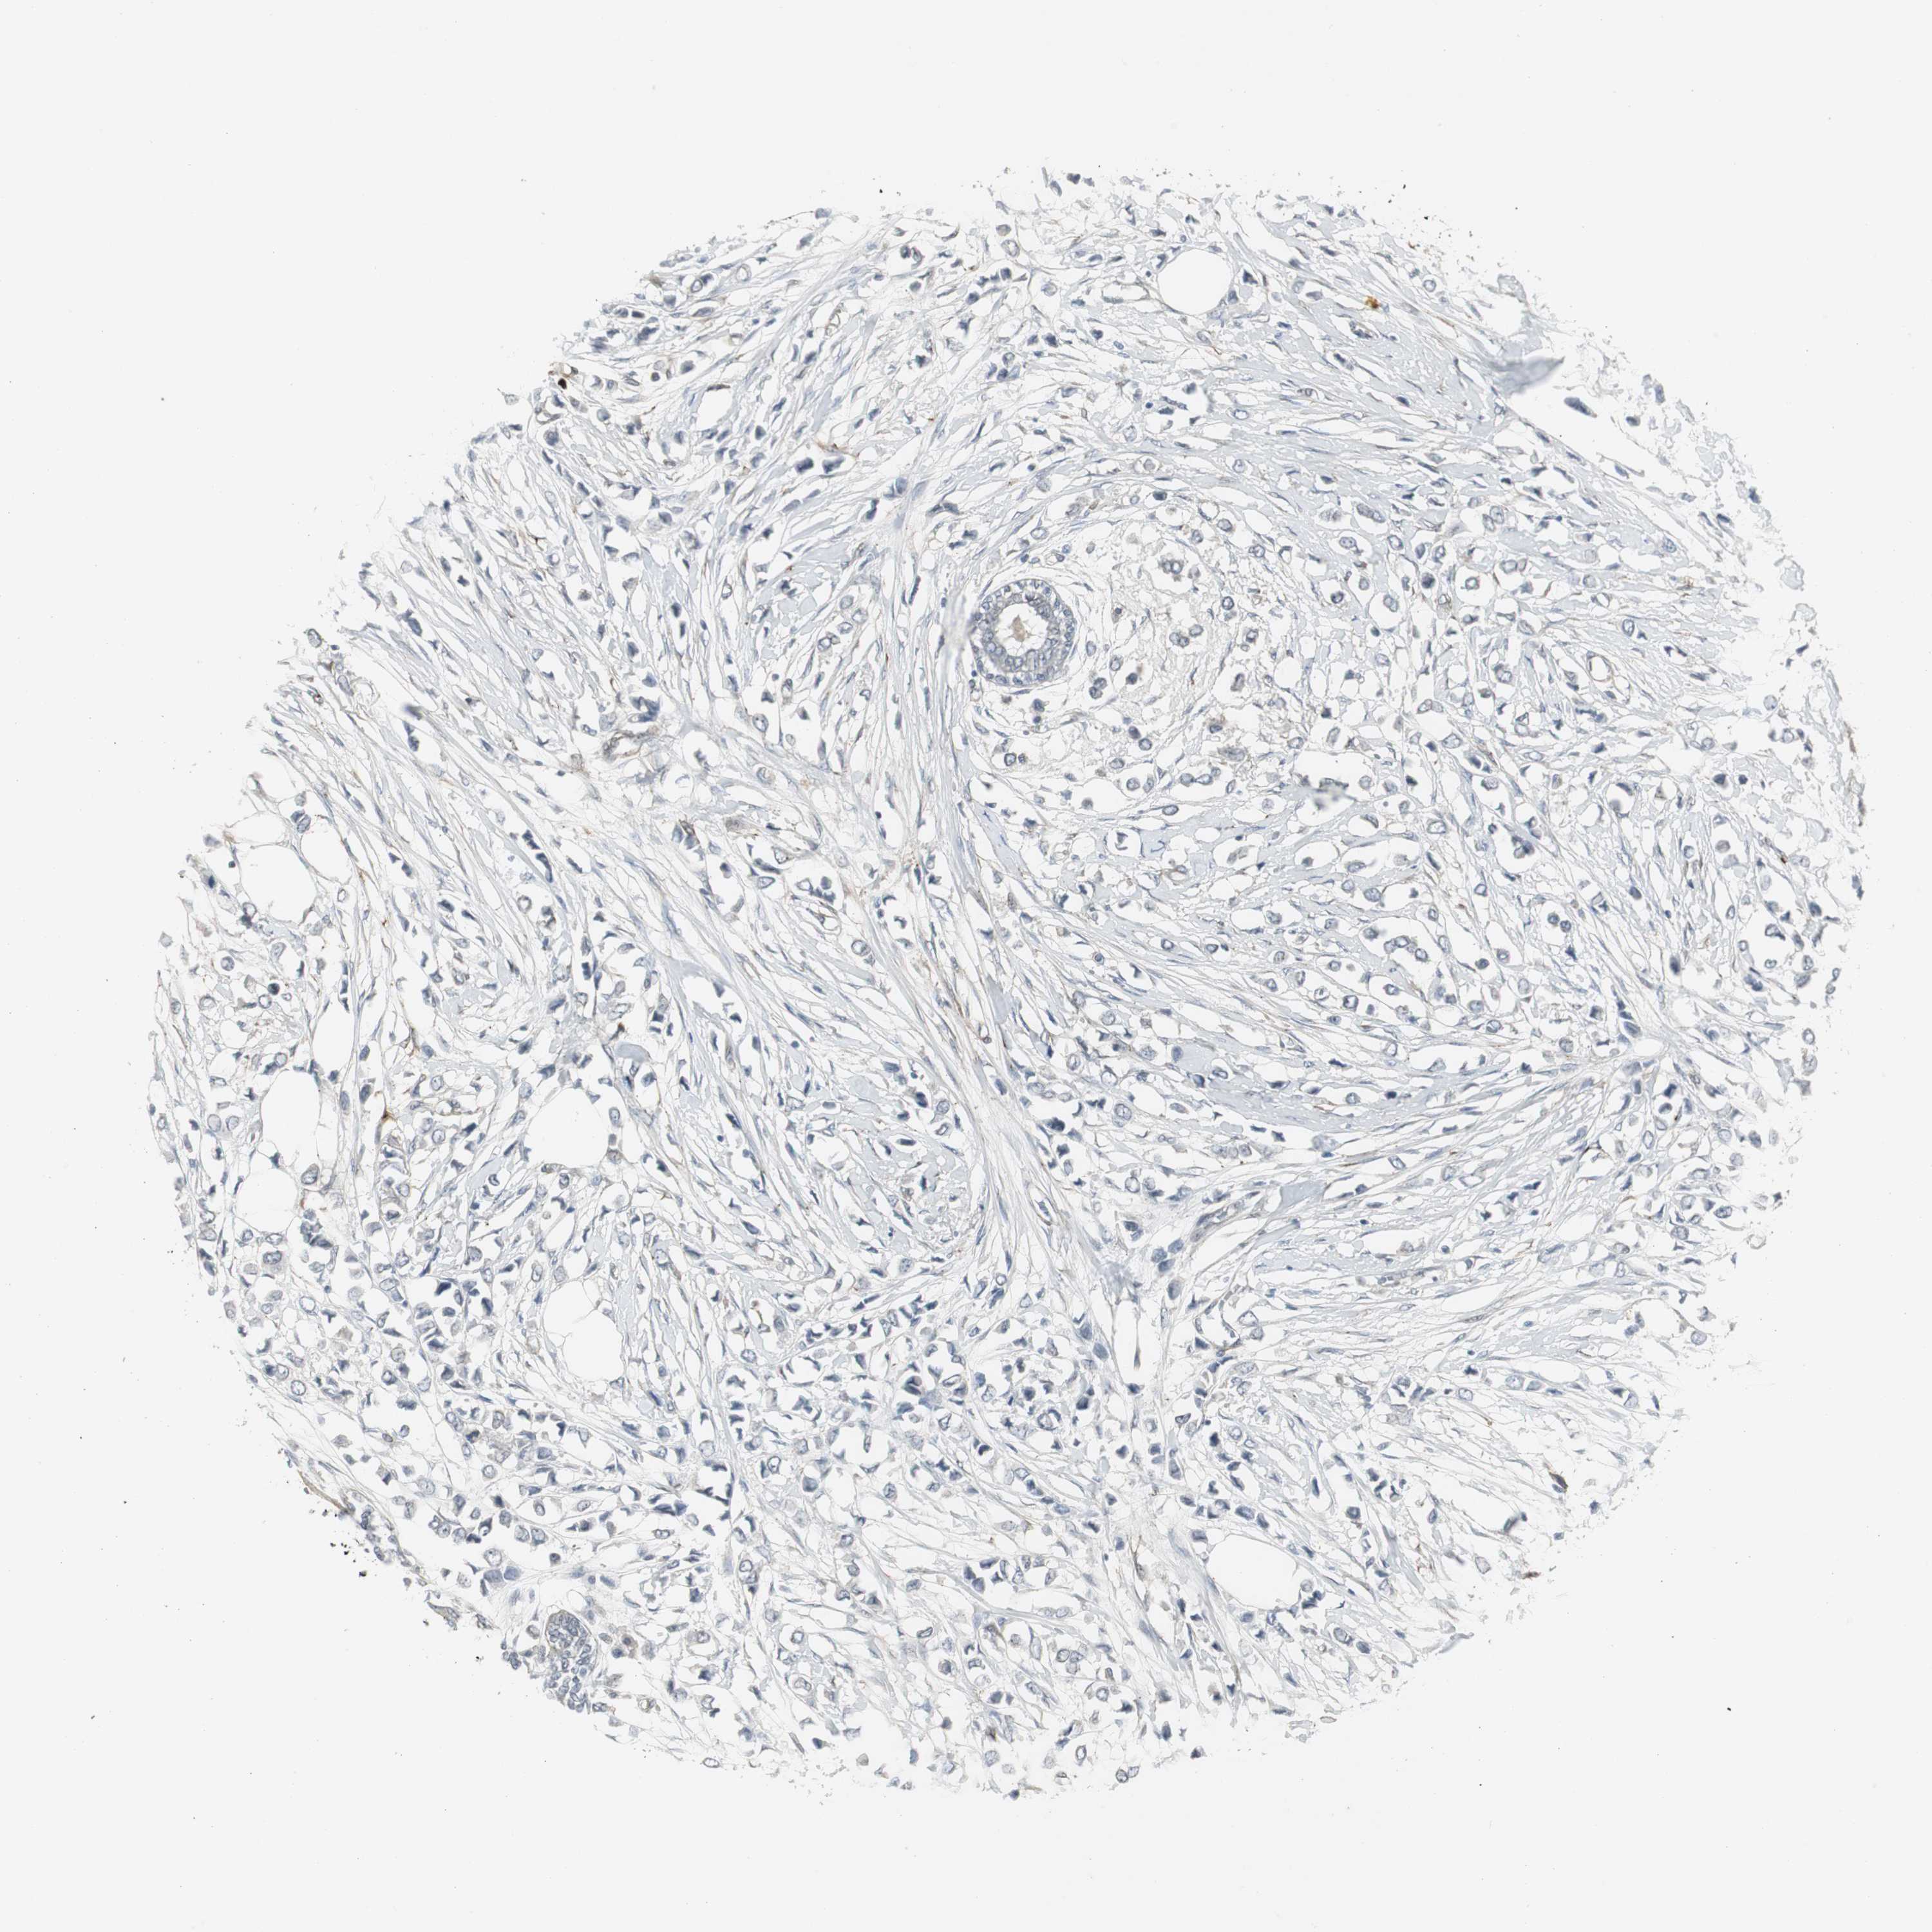

BRCA TCGA BRCA VALIDATION PROTEIN EXPRESSION

ANTIBODIES

AND

VALIDATION